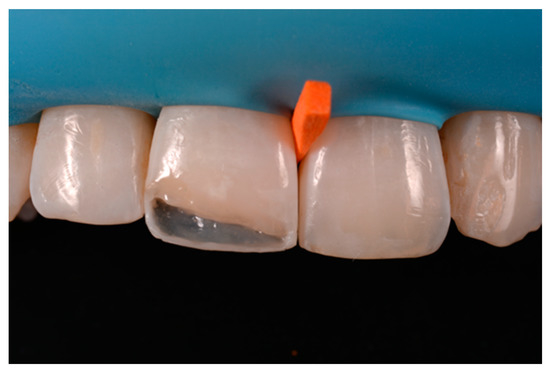

A healthy 38-year-old man referred to the dental office for the esthetic rehabilitation of left central maxillary incisor (Figure 41). Shade was selected as described in previous cases, using the button-try technique [14]. Isolation, preparation (Figure 42) and adhesive procedures were performed (Tokuyama Bond Force, Tokuyama Dental, Osaka, Japan). and Class III was restored on right central incisor (Asteria, A2B, Tokuyama Dental, Osaka, Japan). Frame was then completed on #2.1 (Figure 43) with the use of posterior sectional matrices using translucent and body material (Asteria, NE, A2B Tokuyama Dental, Osaka, Japan). After removing excesses both from the incisal margin and from the interproximal portion (Figure 44) silane and adhesive was applied strictly following the procedure described in Section 2.1.2. Dentinal body (Asteria, A2B, Tokuyama Dental, Osaka, Japan) was applied to reproduce internal anatomy (Figure 45) and then the external translucent enamel (Figure 46) (Asteria, NE, Tokuyama Dental, Osaka, Japan) was applied. The restoration shows good integration 6-months post-operative (Figure 47).

Figure 42.

Preparation of Class III on #1.1 and Class IV on #2.1.

Figure 43.

The frame completed.

Figure 44.

The frame modified either in the incisal frame and in the interproximal wall.